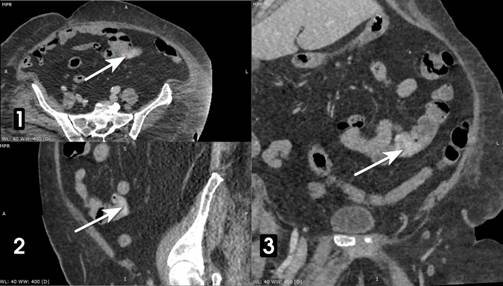

Рис. 2. КТ той же больной через 30 сек.

Стрелками показана экстравазация РКВ вещества в просвет тощей кишки. Аксиальная плоскость (1) и реконструкция в сагиттальной (2) и фронтальной (3) плоскостях. Примечание: составлено авторами по результатам данного исследования